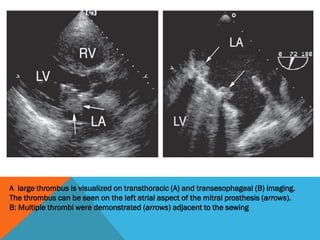

A large thrombus is visualized on transthoracic (A) and transesophageal (B) imaging.

The thrombus can be seen on the left atrial aspect of the mitral prosthesis (arrows).

B: Multiple thrombi were demonstrated (arrows) adjacent to the sewing